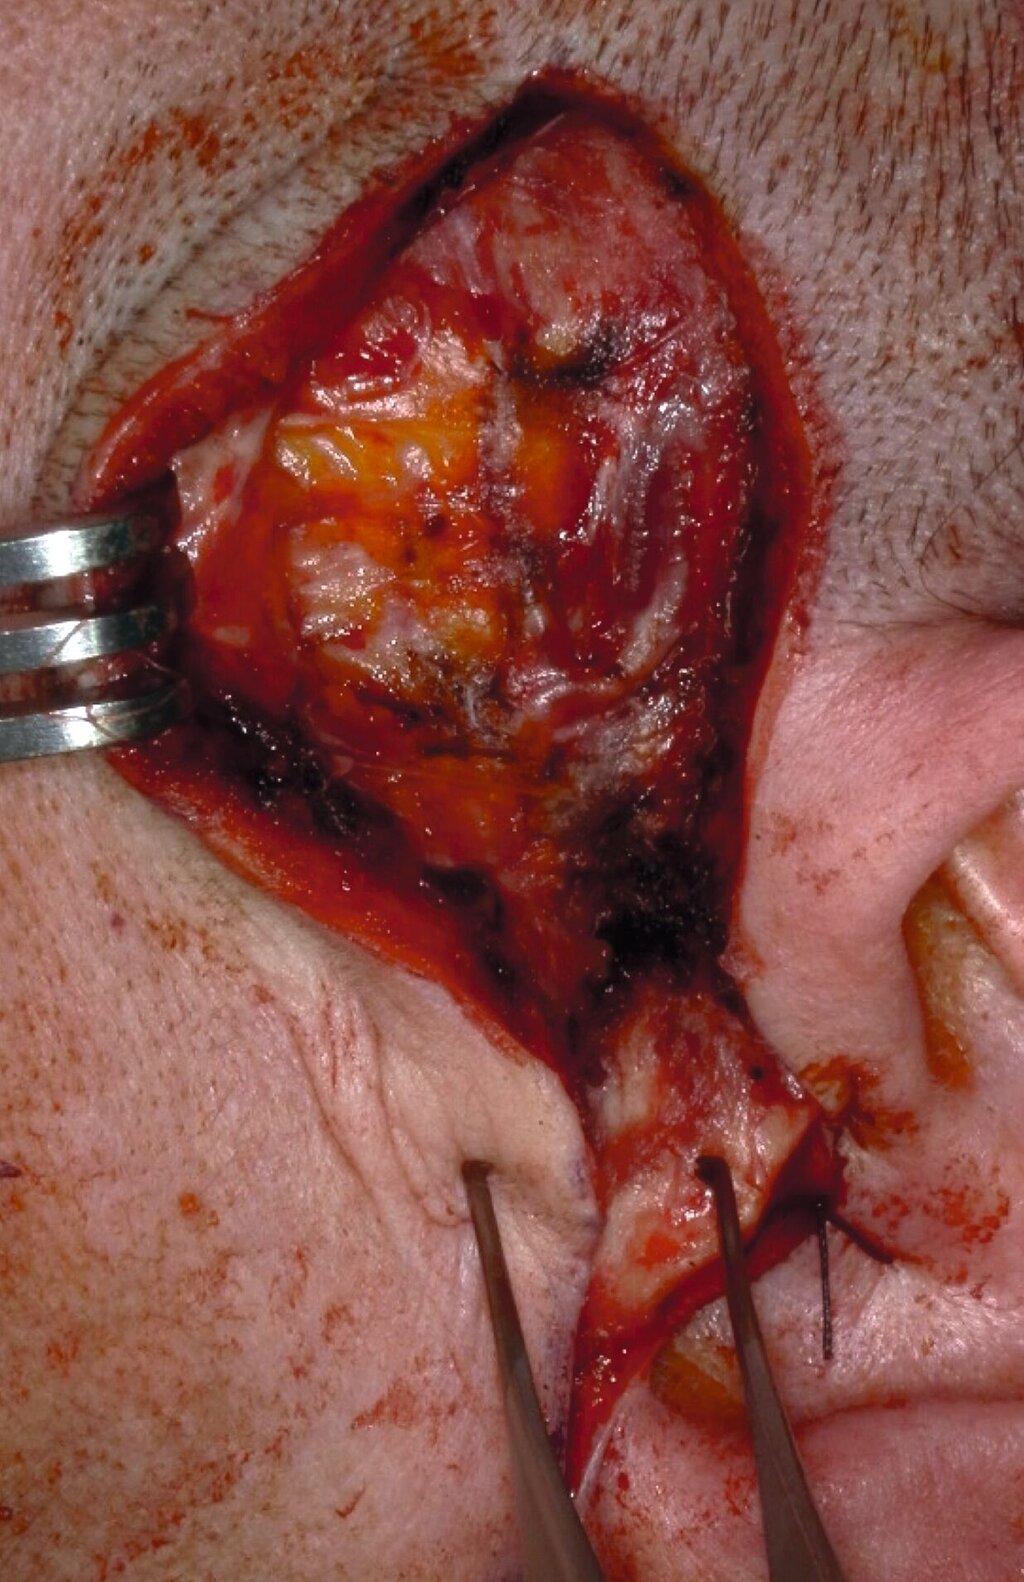

Bei nunmehr erhärteter radiologischer Verdachtsdiagnose auf das Vorliegen einer synovialen Chondromatose erfolgte, entsprechend dem Patientenwunsch, die offen-chirurgische Resektion der multiplen Gelenkkörper in Intubationsnarkose. Der Zugang wurde klassisch präaurikulär mit einer temporalen Extension zum Schutz des Ramus temporalis des Nervi facialis gewählt (Abbildung 3a). Unmittelbar nach Eröffnung der Kiefergelenkkapsel entleerten sich rasch mehrere kleine, knorpelige Raumforderungen (Abbildung 3b), die im Rahmen des Eingriffs vollständig entfernt wurden (Abbildung 3c). Der erweiterte, nun leere obere Gelenkspalt ist in Abbildung 3d dargestellt.